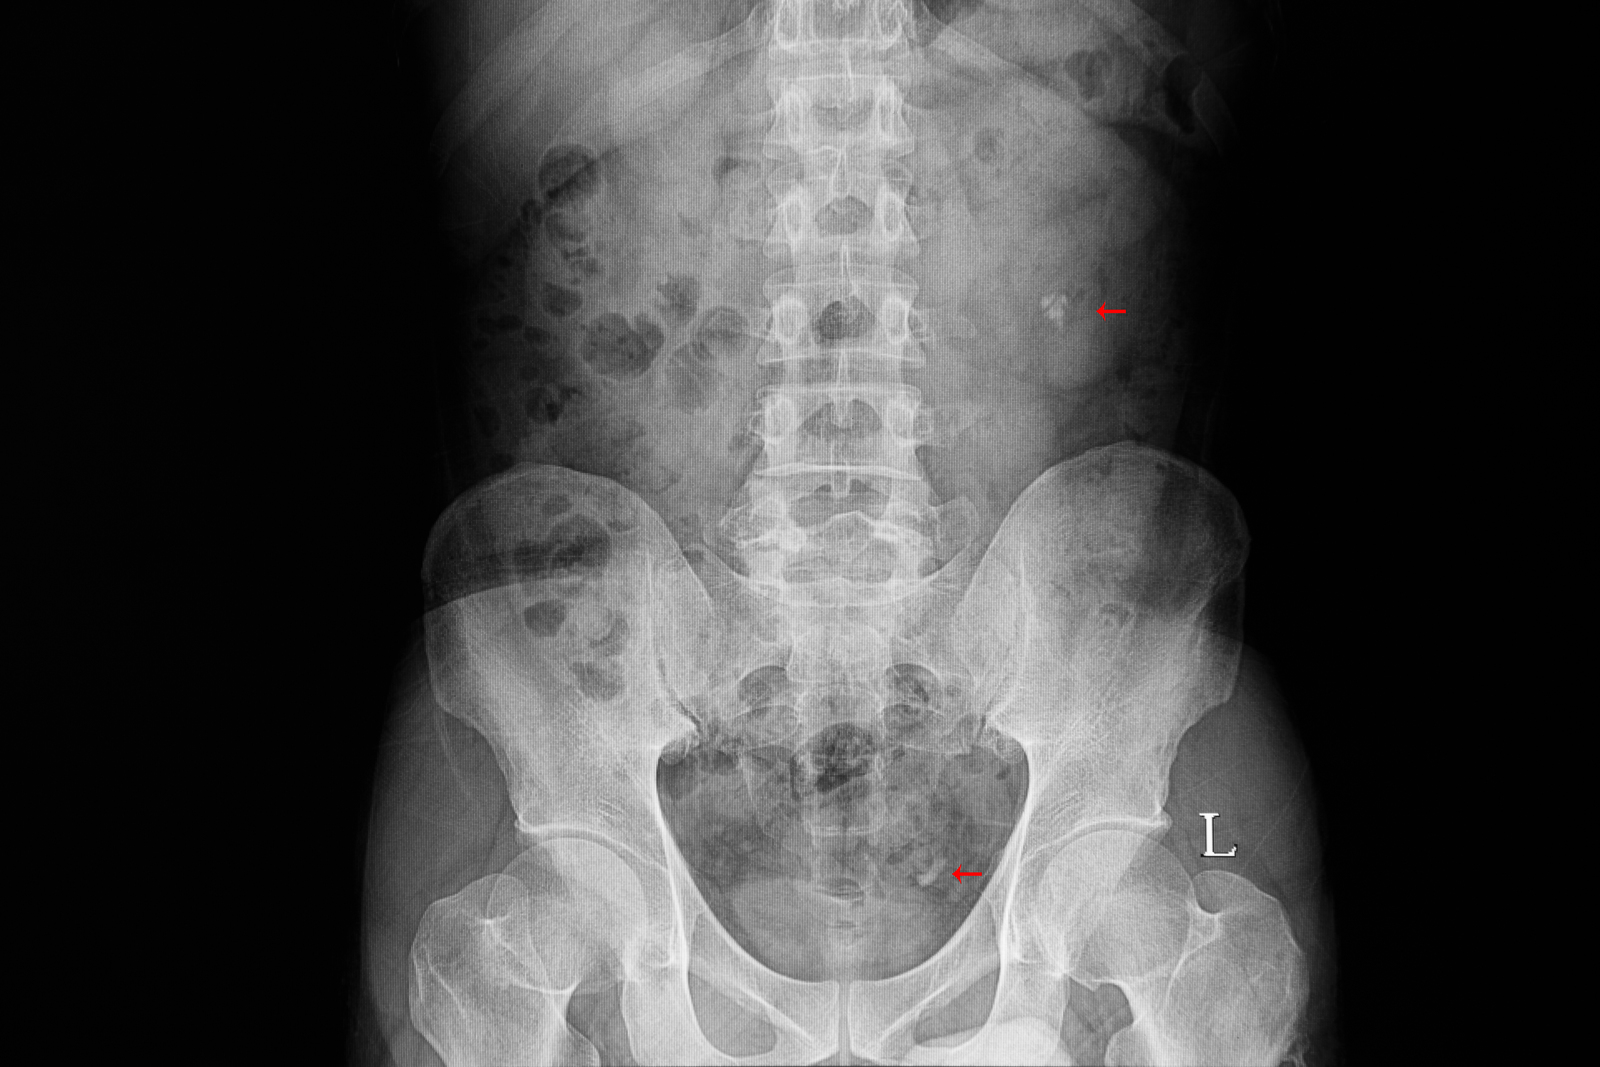

office. It was much closer than a hospital. The medical staff ran a few tests

and took some x-rays. The doctor told me that I had developed kidney stones. I

was shocked and didn't know what to do. I wasn’t familiar with kidney stones and

didn't know how they were formed or how to treat them.